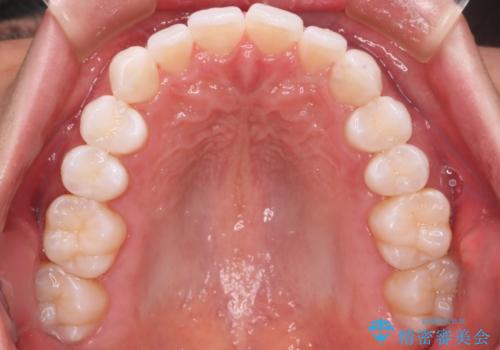

- 20代男性

- インビザライン

- がたつきが気になるとの事で来院されました。

目立たない装置で費用も抑えたいとの希望があったため、インビザラインにて治療をすることとなりました。

上下顎ともにIPR(歯と歯の間を削る処置)を行い歯並びを整える治療計画を立てました。

治療当初は、計画通りに治療が進むか心配でしたが、しっかりマウスピースを使用していただいたことで

治療期間も長引くことなく歯並びを綺麗に改善することが出来ました。

患者様の希望もあり、前歯の微調整で1回リファイメント(マウスピースの再発注)を行いました。